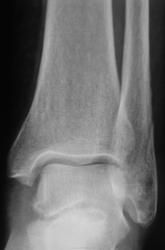

Краевой перелом наружной лодыжки? Интересен механизм травмы.

Перелом наружной лодыжки. Но механизм интересно знать. Футболист, гонитель жён или гандболист и т.д.

перелом то обычный, наружняя лодыжка, а вот н\3 м\б кости подвздута и периостит б\б кости или мне это кажется)

наруж. лодыжки самый банальный ( без смещения).Таких в пору гололёда в день по несколько штук видим. Смутил переостит по передней поверхности малоберц. к.